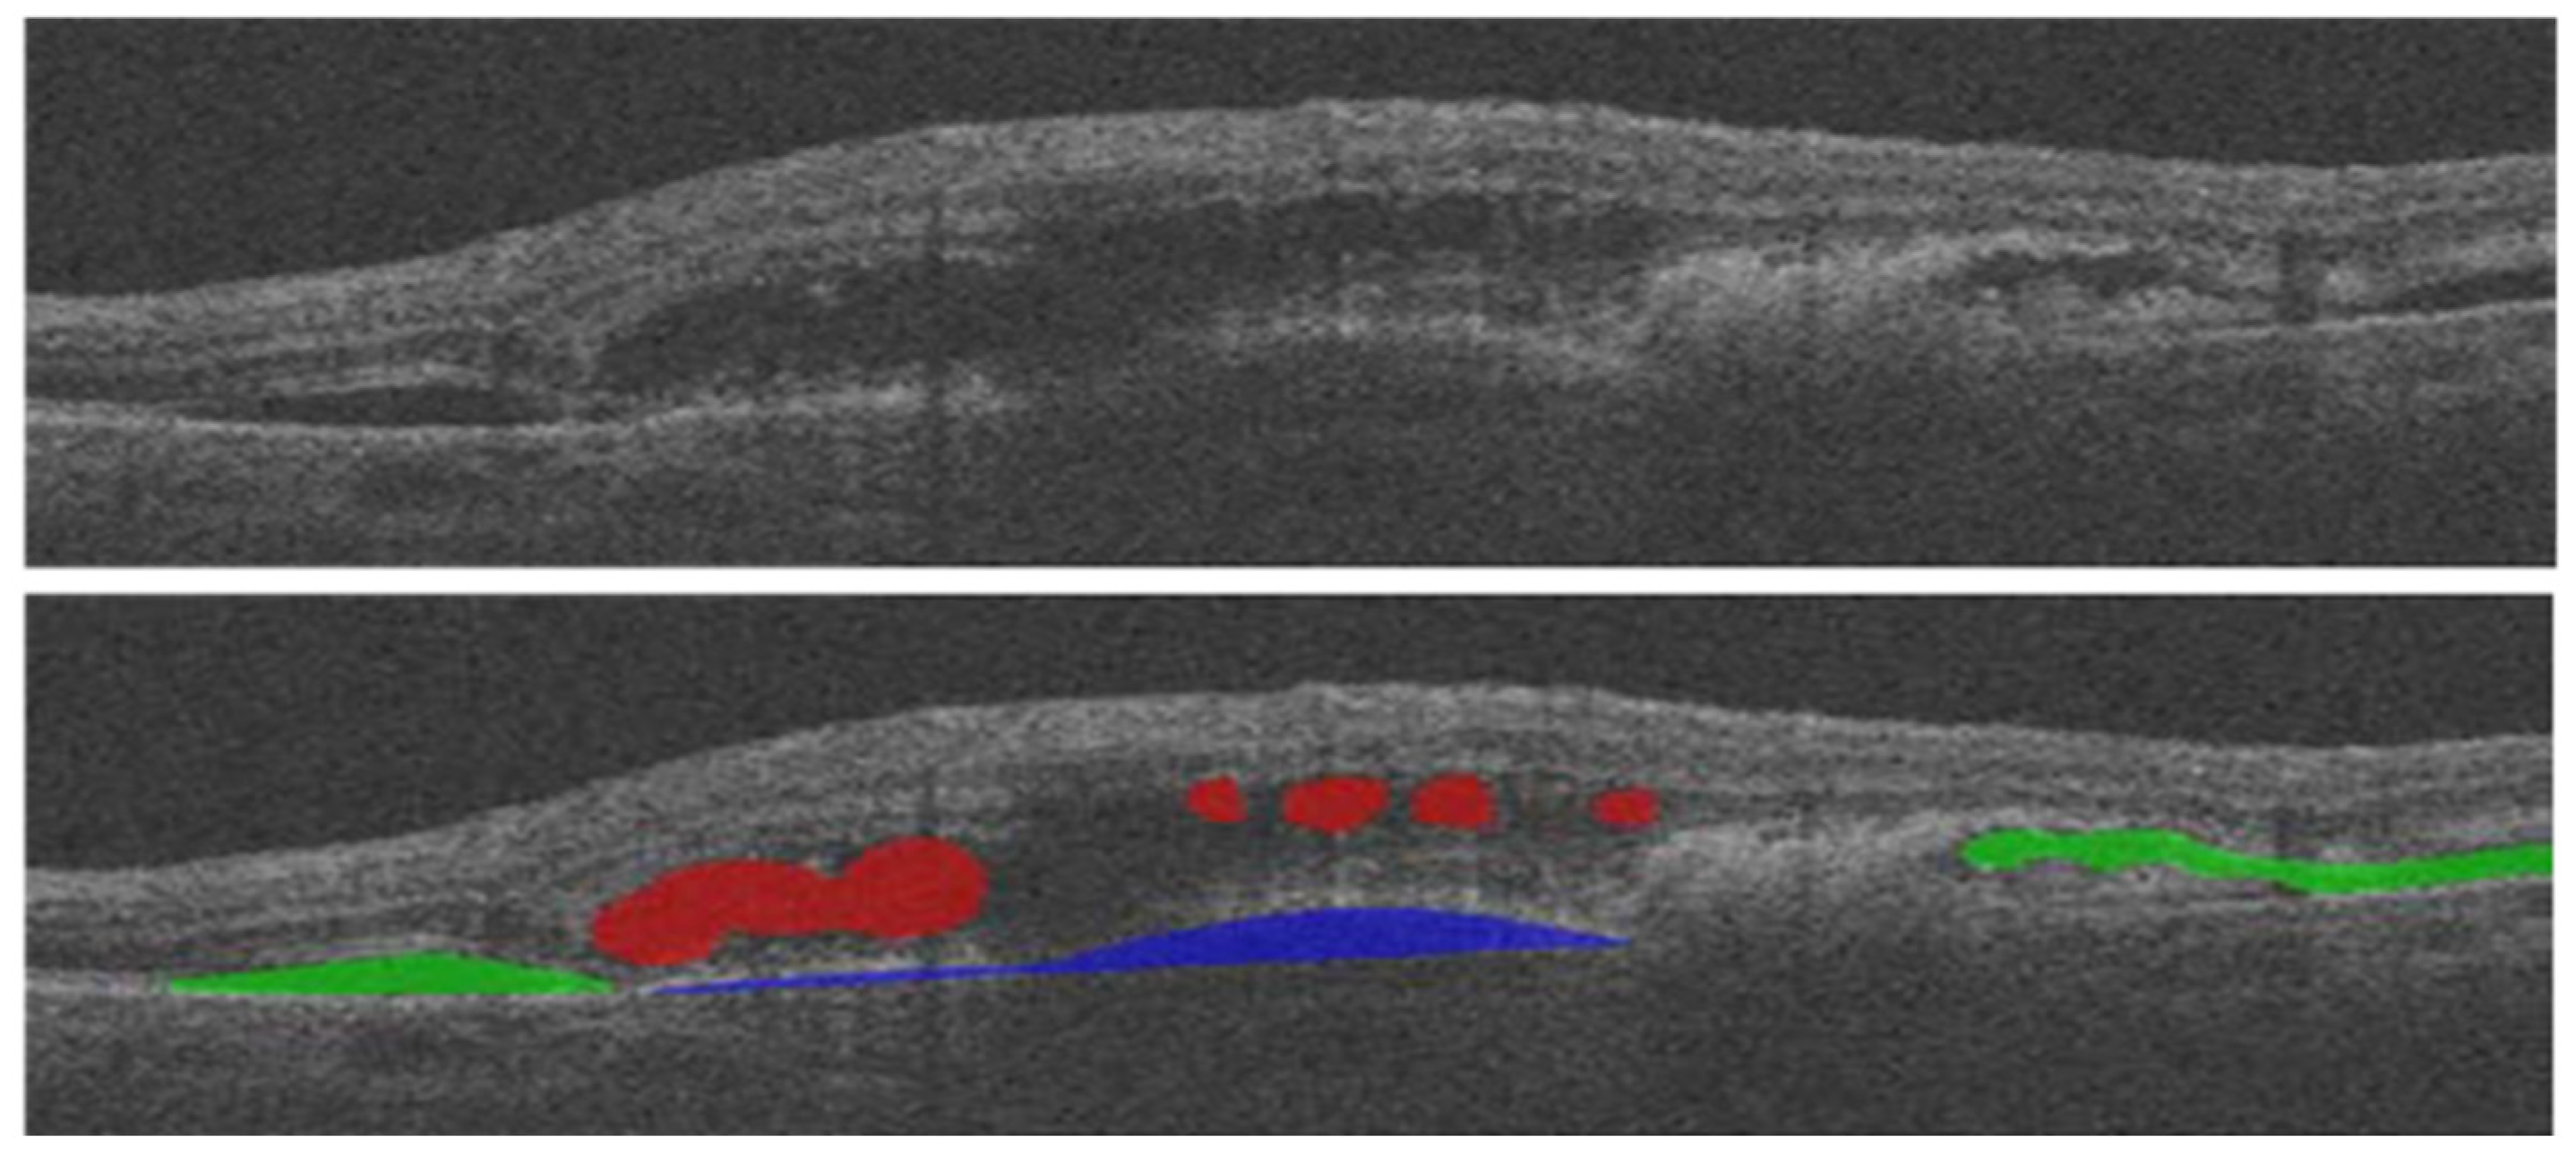

- Zheng, Y.; Sahni, J.; Campa, C.; Stangos, A.N.; Raj, A.; Harding, S.P. Computerized Assessment of Intraretinal and Subretinal Fluid Regions in Spectral-Domain Optical Coherence Tomography Images of the Retina. Am. J. Ophthalmol. 2013, 155, 277–286.e1. [Google Scholar] [CrossRef] [PubMed]

- Chen, Z.; Li, D.; Shen, H.; Mo, H.; Zeng, Z.; Wei, H. Automated Segmentation of Fluid Regions in Optical Coherence Tomography B-Scan Images of Age-Related Macular Degeneration. Opt. Laser Technol. 2020, 122, 105830. [Google Scholar] [CrossRef]

- Guo, Y.; Hormel, T.T.; Xiong, H.; Wang, J.; Hwang, T.S.; Jia, Y. Automated Segmentation of Retinal Fluid Volumes from Structural and Angiographic Optical Coherence Tomography Using Deep Learning. Transl. Vis. Sci. Technol. 2020, 9, 1–12. [Google Scholar] [CrossRef]